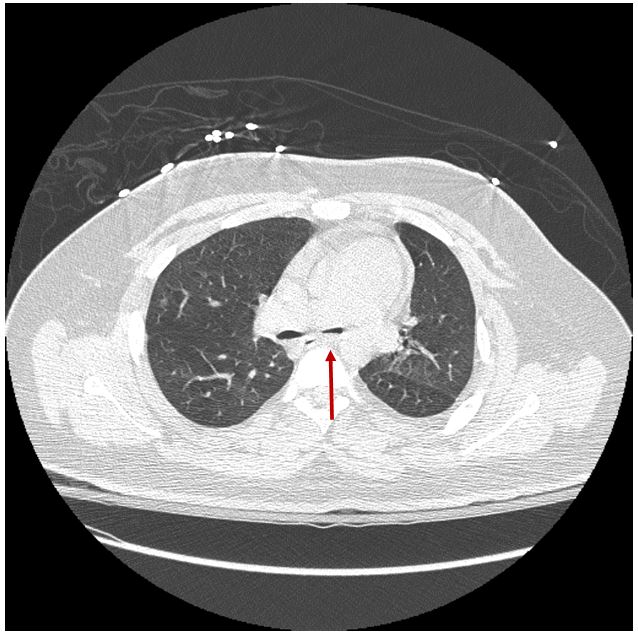

Figure 2.2 CT of the chest showing significant luminal collapse at the level of the carina